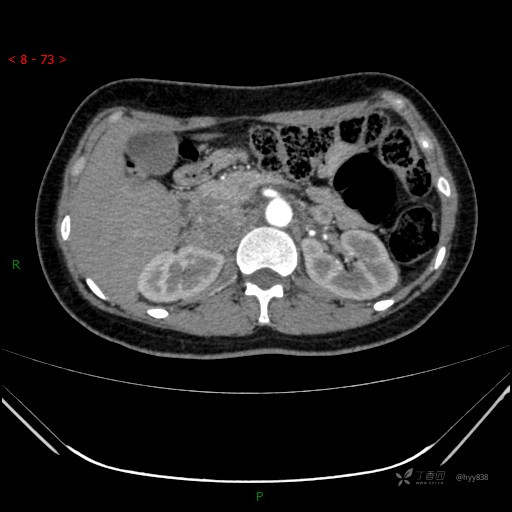

肾上腺CT平扫

动脉期

静脉期